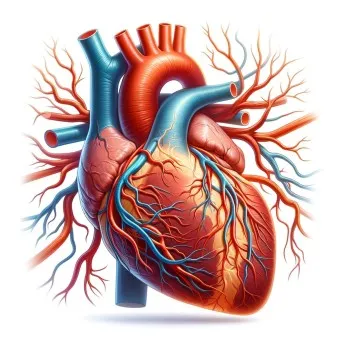

의학적 원인과 진단 기준

때로는 의학적 관심이 필요한 원인들도 있습니다. 전문가들의 연구에 따르면 다음과 같은 경우를 주의 깊게 살펴봐야 해요:

1. 심장 관련 원인

- 부정맥: 정상 심박수 범위 60-100회/분 이탈

- 심장 판막 이상: 증상 발현 시 심박수 변동 20% 이상

- 빈맥증: 휴식 시에도 심박수 100회/분 이상

- 서맥증: 심박수 60회/분 이하로 저하